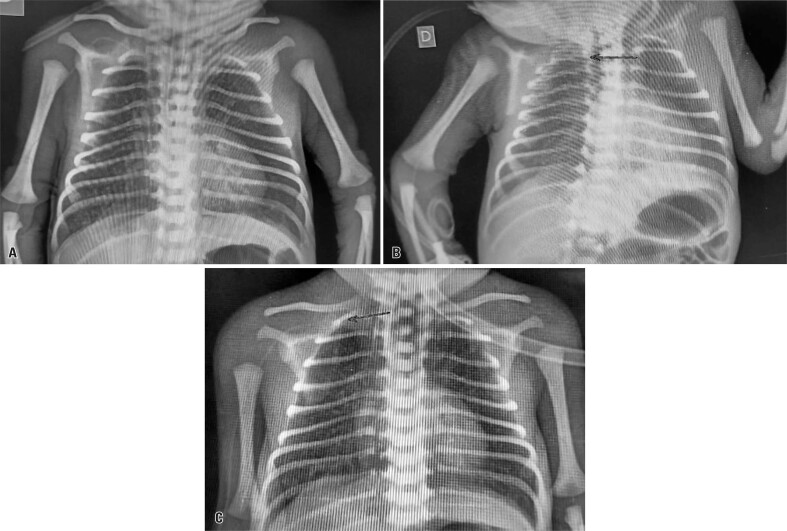

背景:这篇文章描述了在巴西的一所大学医院,一个早产儿在使用外周插入中心导管后发生心脏填塞。行心包穿刺,经x线摄影重新定位导管,超声心动图证实心包积液残留极小。患者进展良好,并于生命第47天出院,无任何与该事件相关的并发症。因此,尽管在置入外周中心导管后可能发生不良事件,但影像学检查和排除诊断对临床结果有积极影响。本研究强调了多学科团队对监测和管理不良事件以及优化危重新生儿护理的重要性。

Background: This article describes the occurrence of cardiac tamponade in a premature newborn after the use of a peripherally inserted central catheter at a university hospital in Brazil. Pericardiocentesis was performed, the catheter was repositioned using radiography, and minimal residual pericardial effusion was confirmed using echocardiography. The patient showed good progress and was discharged from the hospital on day 47 of life without any complications related to the event. Therefore, although adverse events may occur following the insertion of peripherally inserted central catheters, imaging examinations and exclusion diagnoses have a positive impact on clinical outcomes. This study emphasizes the importance of a multidisciplinary team for monitoring and managing adverse events and optimizing the care of critically ill newborns.